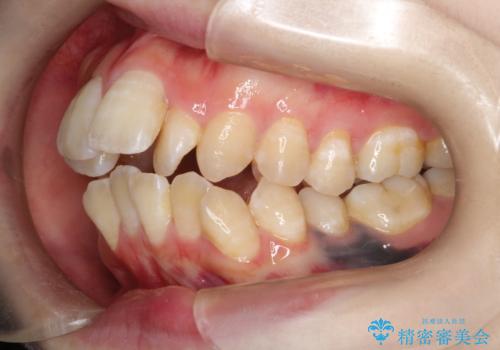

重度のガタガタ ワイヤーによる抜歯矯正

- 出っ歯と全体的ながたつきを主訴に来院されました。

上下の歯に重度のガタガタがあり、前歯が下の歯と咬んでいない状態でした。

審美装置を用いた、抜歯矯正を行うこととしました。